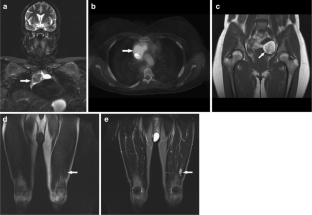

Incidental findings other than scoliosis were recorded in 104/247 (42%) patients, most often affecting the musculoskeletal system (65/247 patients, 26%). We found 16/247 (6.5%) significant incidental findings likely to affect clinical management, including avascular necrosis of bone in eight patients (five with NF2), eight insufficiency fractures, and four non-neurogenic neoplasms (Hodgkin's lymphoma, liposarcoma, dermoid cyst, large uterine myoma requiring excision). Scoliosis was seen in 50/247 patients (20%), including 8/55 with NF2 (15%) and 11/51 with schwannomatosis (22%).